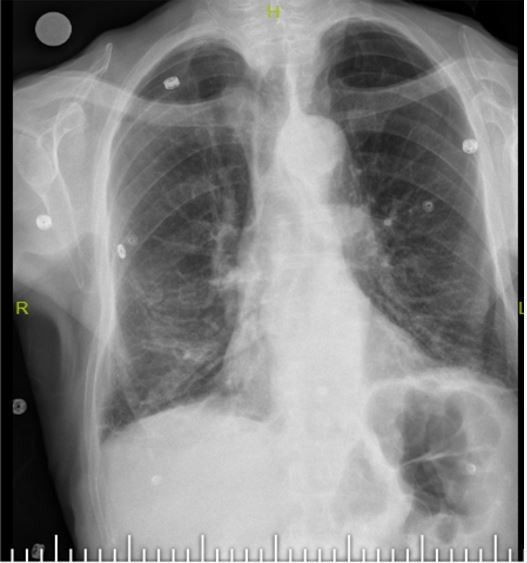

Elazığ'da yaşlı adamın boğazından 10 Santimetrelik çivi çıkarıldı - Resim: 2

Bu nedenle gelişen öksürük ve nefes darlığı şikayeti ile önce başka bir sağlık merkezine başvurmuş, ardından Fethi Sekin Şehir Hastanemiz Göğüs Cerrahisi Kliniğine yönlendirilmiş. Biz de hastanede 91 yaşındaki hastamıza çektiğimiz tomografide soluk borusu içerisinde, sağ akciğer içerisine doğru kaçmış olan çiviyi tespit ettik” dedi.

Bunun üzerine hastayı acil olarak ameliyata aldıklarını aktaran Kılıç, “Uyguladığımız Rijit Bronskoskopi işlemi ile nefes borusundaki 10 santimetrelik çiviyi başarılı bir şekilde çıkardık.

Hastamızı ameliyat sonrası bir süre serviste takip ettikten sonra gün içerisinde şifa ile taburcu ettik. Nadir de olsa bu tarz durumlarla karşılaşıyoruz. Bu tür durumlarda hızlı müdahale etmek oldukça önemli. Trakeostomili hastaların bu şekilde yabancı cisimlerle soluk borusuna müdahale etmemeleri gerekiyor” diye konuştu.